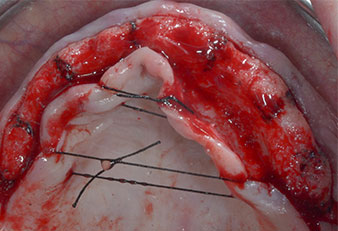

Три години по-късно е дошло времето за максиларна протеза от същия тип. Въз основа на планирането със CBCT, аугментацията на синусите е избегната с помощта на къси импланти и използването на хирургичен шаблон, за да се прехвърлят планираните позиции в алвеоларния гребен. (Фиг. 1 и 2).

Пиезоелектрически инструмент с диамантено покритие с форма на пламък (Piezomed I1) e използван за маркиране на позициите на имплантите и за пилотна подготовка (Фиг. 3). Препарацията беше извършена с внимателни вертикални движения, с намалена мощност, пълна иригация и лек натиск (под 300 g) След това се приложи пилотен инструмент (Piezomed I2A/ I2P) за първоначално увеличение на диаметъра на имплантното ложе с 2 mm (Фиг. 4), последвано от 3 mm разширение (Фиг. 5)